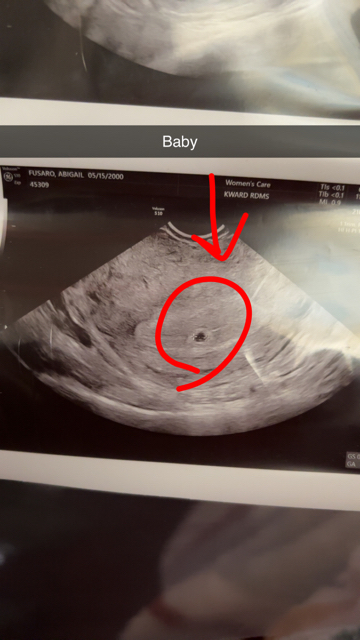

Found out I was pregnant about a week ago, I called my ob and I had an appointment set up for April 18. Well yesterday I was having very light spotting but period like cramps and back pain. Naturally I freaked out and went to my nearest ER. They ran blood and urine tests, did a vaginal exam, and did an ultrasound. The ultrasound specialist said that I’m about 4 weeks 5 days and I saw a very small circle on the ultrasound. She called it a yolk sack. She then said that there’s fluid on my uterine lining. Later on the doctor came in and told me that I had no infections and that my tests came back good. But that my hCG beta quantitative was at 443 and it should be in the thousands and that it isn’t consistent with what the ultrasound was measuring. He told me that the fluid on my uterine walls could be blood, but that he wasn’t sure. He then told me that he thinks I’m in the early stages of a miscarriage. I then called my ob and they said they wanted to reorder the tests and would like to confirm the miscarriage before anything is final. She seemed doubtful that I was having one and told me not to stress. Had my appointment with my ob and they did a blood test to see my hCG and progesterone levels. My hCG came back at 881 and my progesterone came back at 13.1. This is a picture of my ultrasound from today. OB said she doesn’t know if I’m going to have a miscarriage as I’m super early. I’m just stressed is all.